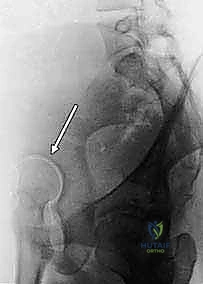

2. الأشعة السينية (X-Rays): قياس زوايا محددة مثل زاوية ويبرج (Wiberg CE Angle) وزاوية ميل سقف الحق (Tonnis Angle) لتقييم مدى التغطية العظمية.

3. التصوير المقطعي المحوسب (CT Scan) ثلاثي الأبعاد: يوفر خريطة طوبوغرافية دقيقة للحوض، مما يسمح للجراح بالتخطيط الدقيق لمقدار وزاوية التدوير المطلوبة للتجويف الحقي.